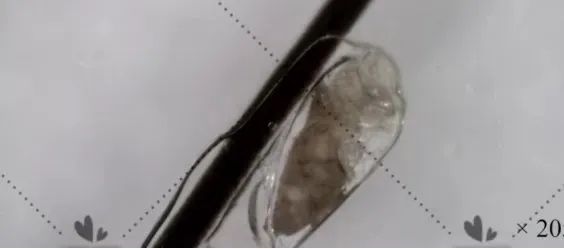

这种白色物质是毛发管型

毛发管型是包绕着发丝的管状附着物,会自由移动,但不会传染,也不会让人感觉头皮疼或者痒。

受损的外根鞘和残留角化不良的内根鞘“联手”包绕毛干,由此形成的角质套就是我们说的“毛发管型”。